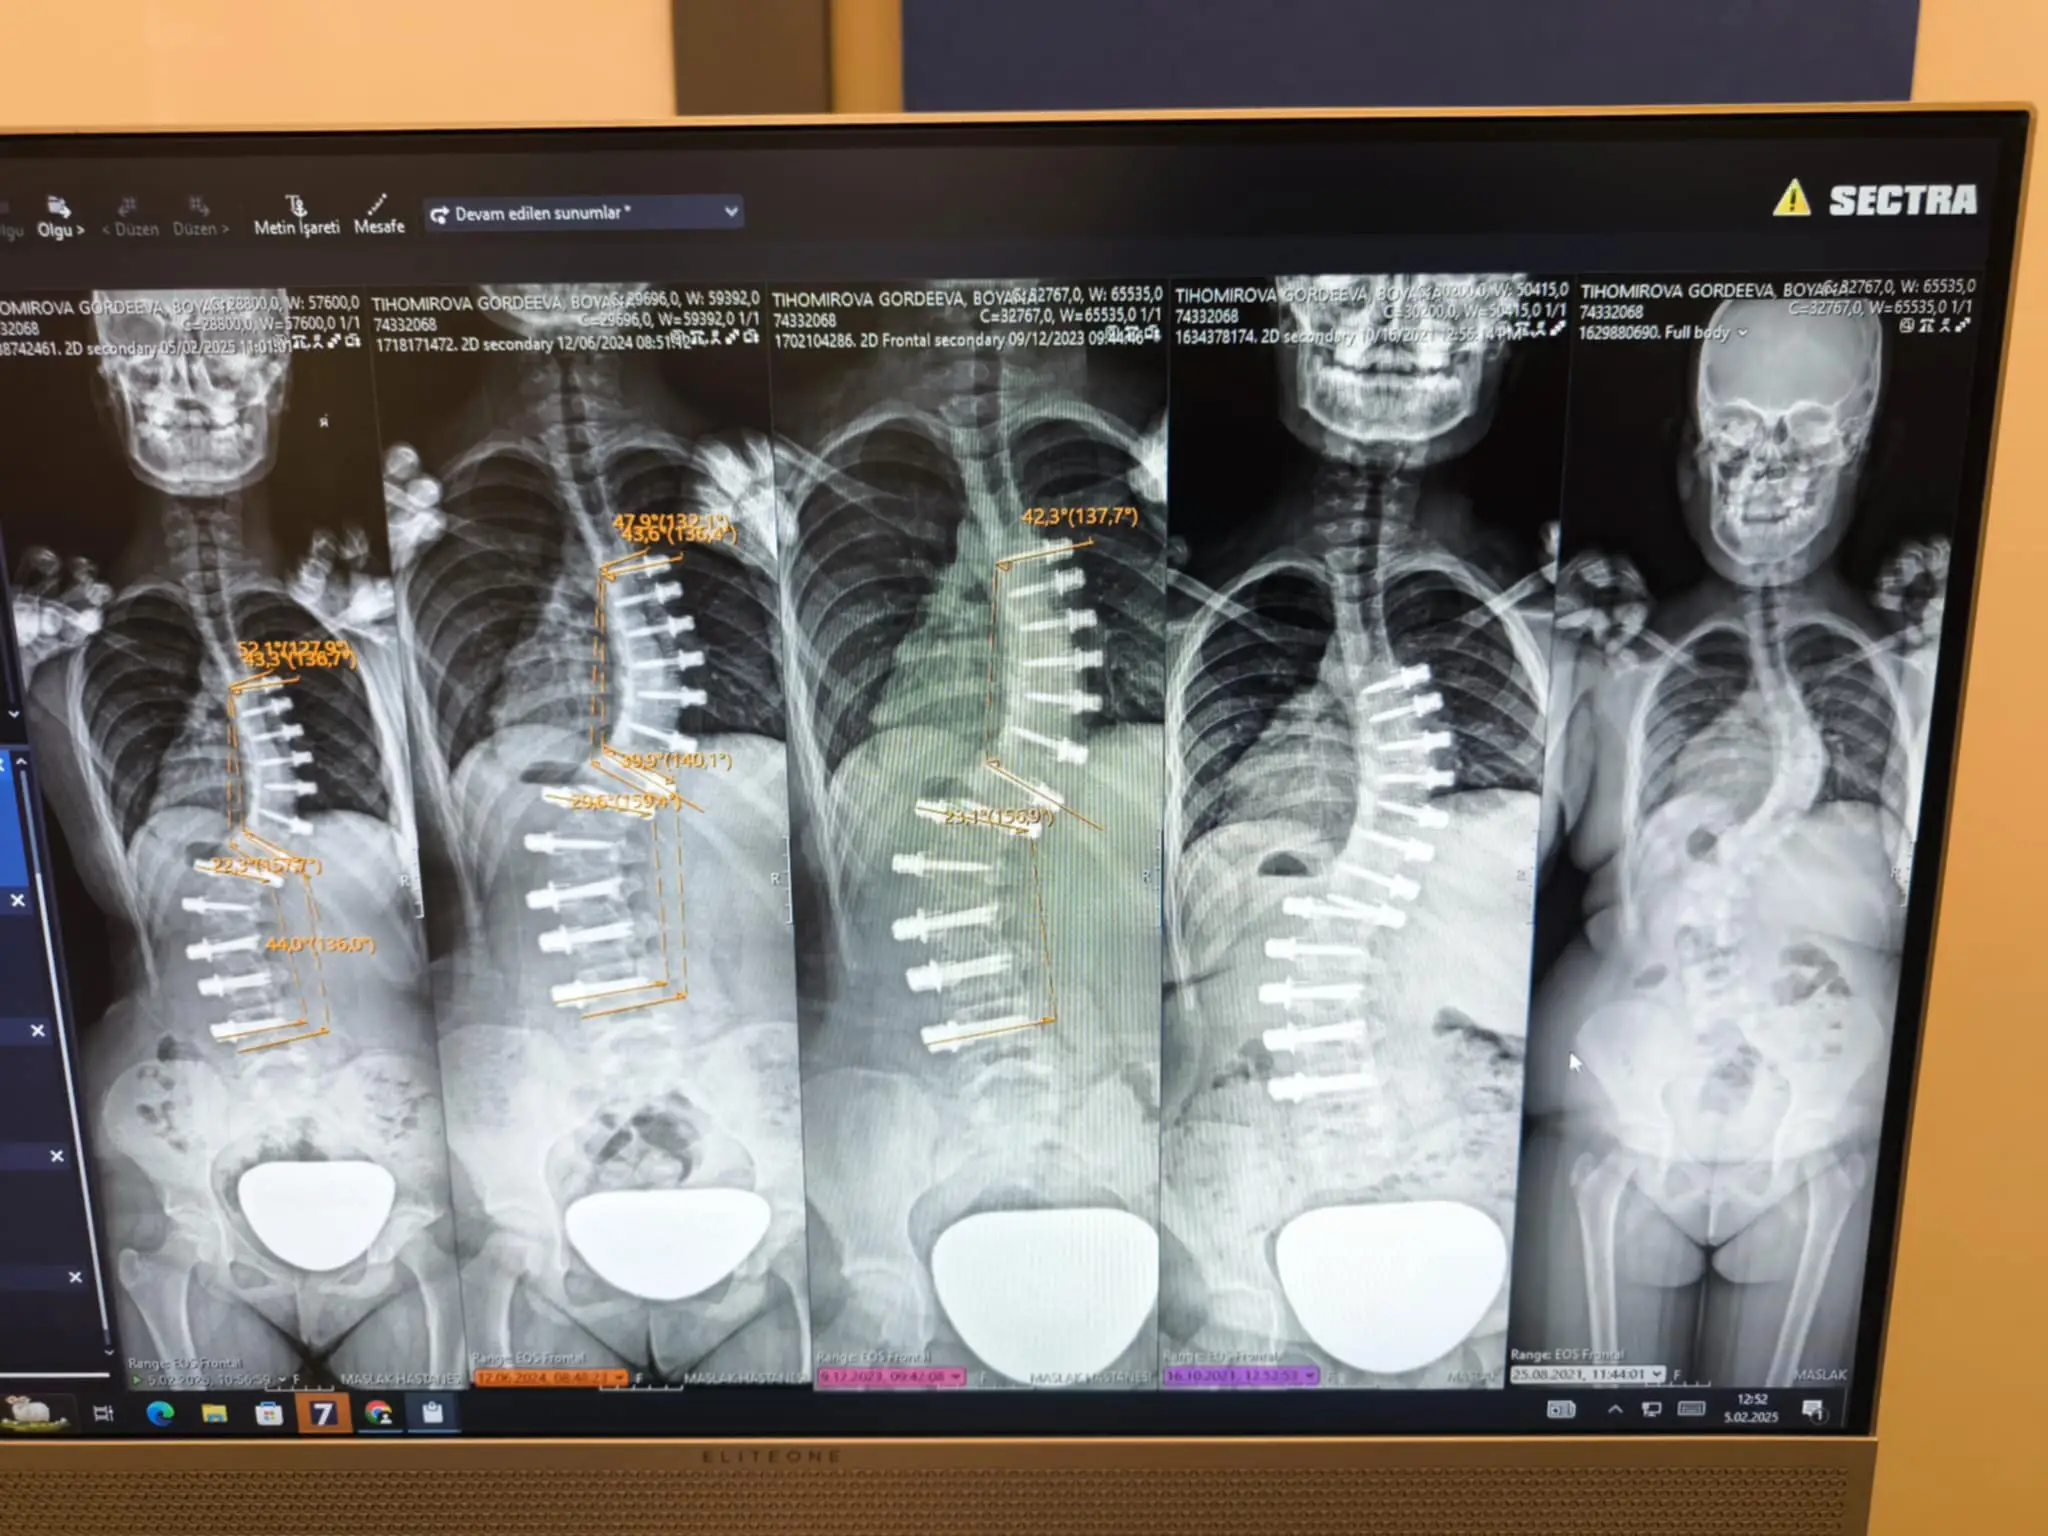

На 9 години претърпя първата си операция в Аджибадем Маслак, Истанбул, извършена от проф. Ахмед Аланай по иновативния метод VBT (Vertebral Body Tethering). За съжаление, след инцидент кордата се скъса и кошмарът започна отново – нови корсети, ново чакане.

Днес Бояна е висока 171 см, но кривината продължава да расте. На 12.11.2025 г. след пореден преглед проф. Аланай беше категоричен: без ревизионна операция състоянието ѝ ще се влошава и всичко постигнато досега ще бъде загубено.

At the age of 9 she underwent her first surgery in Ajibadem Maslak, Istanbul, performed by Prof. Ahmed Alanay under the innovative VBT (Vertebral Body Tethering) method. Unfortunately, after an accident the cord broke and the nightmare started again - new corsets, new waiting.

Today Boyana is 171 cm tall, but the curvature continues to grow. On 12.11.2025 after another examination prof. Alanay was adamant: without revision surgery, her condition will worsen and everything achieved so far will be lost.